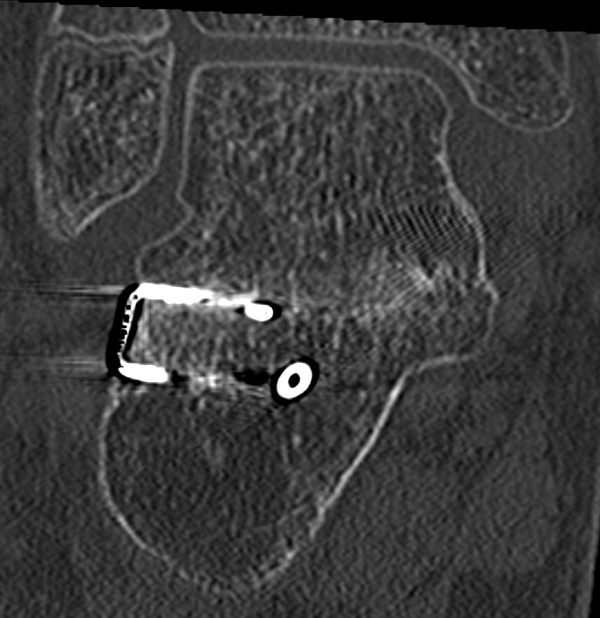

Auf dem Bild zu sehen die chirurgisch dargestellte Coalitio Calcaneo naviculare unmittelbar vor der Resektion Copyright Dr S Böhr